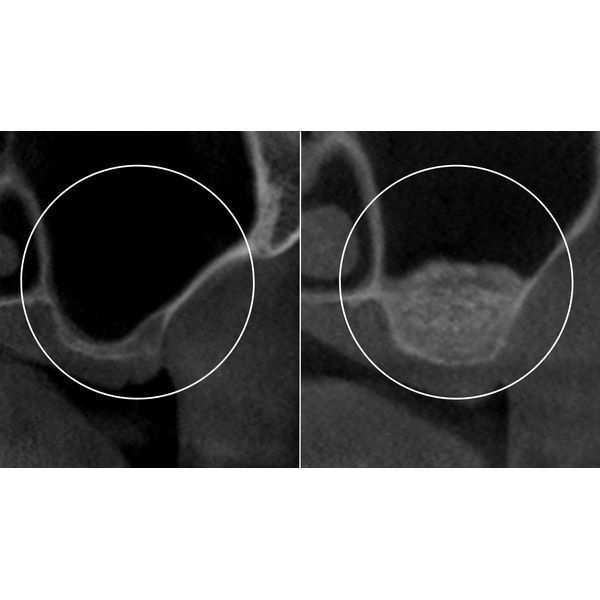

Женщине провели 3D-диагностику, чтобы оценить состояние твёрдых тканей в месте будущей имплантации.

До установки импланта нужно было провести остеопластику, а именно синус-лифтинг. Из-за долгого отсутствия зуба и атрофии кости выбран открытый тип процедуры, который позволяет быстро и надёжно восполнить костную ткань.

Во время синус-лифтинга пациентке под анестезией разрезали десну, просверлили отверстие в боковой стенке гайморовой пазухи и ввели в это «окошко» специальный материал для восстановления объёма костной ткани. Открытый синус-лифтинг предполагает отсроченную установку имплантов, поэтому после операции женщине наложили швы и отпустили её домой.

После открытого синус-лифтинга обычно кость восстанавливается в среднем за 3–6 месяцев. В данном случае костный материал успешно прижился за полгода. Весь этот период пациентка наблюдалась у врача для контроля состояния.